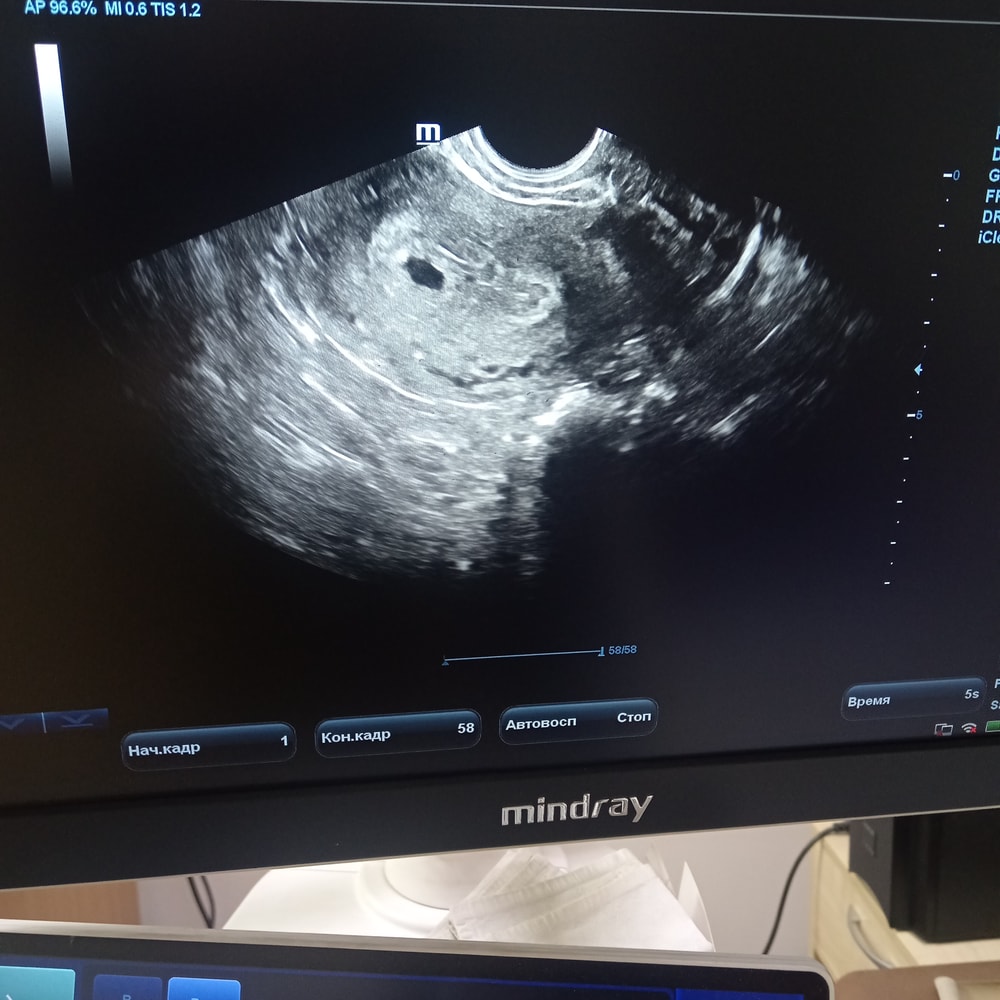

Была сегодня на узи. По месячным срок 5н2д. А по УЗИ сказали 4 недели. Вопрос когда на учёт идти в вставать 🤷

Первый день последних месячных указала 5 ноября, но 2 дня просто мазало. 7 ноября начались обильные. Тест на овуляцию положительный 20 ноября. Считаю, что овуляция была 21 ноября. 11 декабря на узи плодное яйцо 3,8 мм. Желточного мешочка не видно. Перелопатила весь интернет. СВД плодного яйца расстраивает( поддержка утрожестаном 200*2)